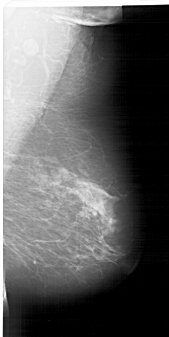

A_1335_1.LEFT_MLO

LEFT_MLO LINES 6796 PIXELS_PER_LINE 3361 BITS_PER_PIXEL 12 RESOLUTION 43.5 OVERLAY